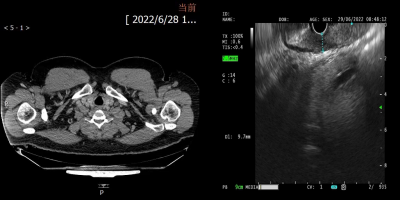

2.png

吴寒经过CT、胃镜等全面检查后,确诊食管下端低分化腺癌 cT3N0M0 III期